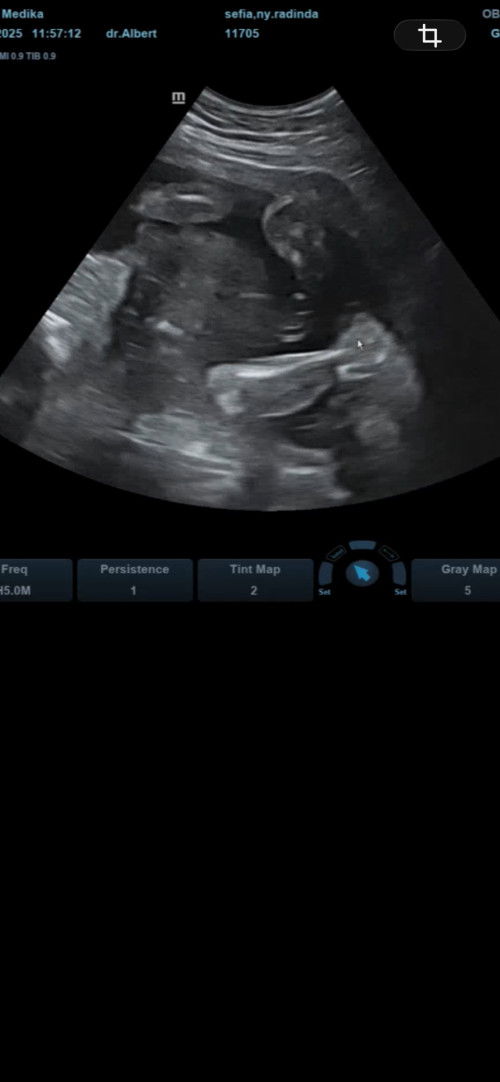

Baby cewe kah ini?

Bun sharing dong yg baby nya cewe, hasil usg nya kek gini kah, Sama kek kek punyaku? Soalnya 2kali usg katanya cewe, dilihat di 4d juga gaada monasnya#bantujawab #sharing #firstmom